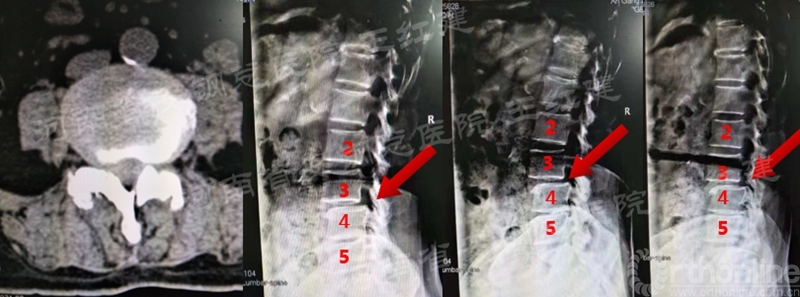

术前

术后

置入内镜通道,用磨钻和枪钳切除上位椎板下缘、下位椎板上缘及突间关节内缘,切除黄韧带,完成单侧入路双侧减压。